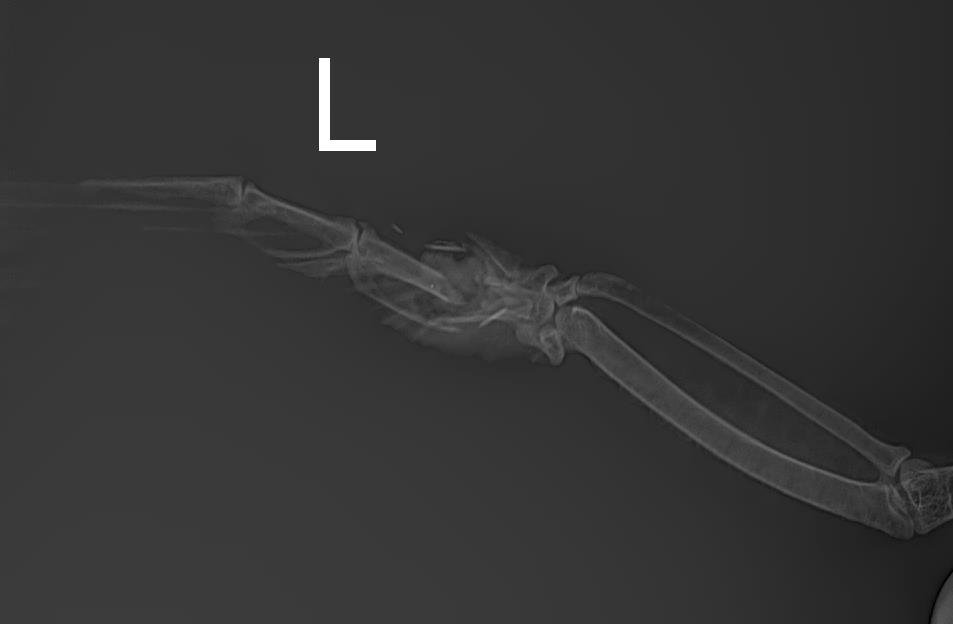

Кости увы в смятку🥺IMG-20250304-WA0032.jpg.dfcfaf83186038116afa74ba775a3e6d.jpg

В очередной раз попытались зафиксировать крыло, но тщетно, буянит, падает и начинает брыкаться-все сползает.

Ещё, делали несколько снимков, к сожалению скинули только этот, на другом снимке были видна зерна в зобе, зоб на ощупь не большой, но зерна немного прощупывались, хотя снимок делали ориентировочно в 6 вечера, а последняя принудительная кормешка была утром в 6.00.

У него с пищеварением проблемы получается , что так долго зерно в зобе?

Вердикт врачей (в другой клинике) такой - только ждать и надеяться. Рана выглядит хорошо, ее врачи осмотрели и обработали, сказали что пока все хорошо, и два известных варианта развития событий - как-то срастётся или же начнется гангрена. Посоветовали ампутировать, но не в таком состоянии как сейчас, что сам не ест и не пьет.